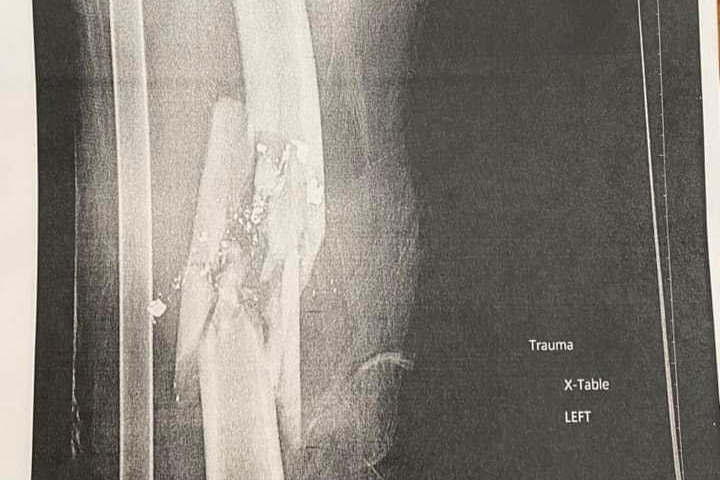

I want to thank everyone for reaching out and continuing to send prayers, well wishes and positive energy Jacob’s way. Here is a summary of what happened: Tuesday evening, November 24th, Jacob and his roommate, Cam, were riding their motorcycles back to Phoenix after a day at the Grand Canyon. Close to Flagstaff, a man who was walking down the median of the interstate shot Jacob in the leg with a 9MM handgun and shattered his femur as they were riding past. Not much traffic or other people around. Jacob immediately knew something hit him and his leg was broken. He was able to keep his motorcycle upright and pull to the side of the road where Cam helped him to the ground. If he would have dropped that bike at highway speed with that injury he most likely would not have survived. He had emergency surgery and now has a rod and screws to hold the pieces together. The bullet was a hollow point, so it disintegrated when it hit the bone. The police found the gun. Later they found the man. Jacob is home in Phoenix, and I’m here with him, and we will be coming home to Omaha soon. He has a long road of healing, but this young man is so strong. Even the doctors were amazed with him.